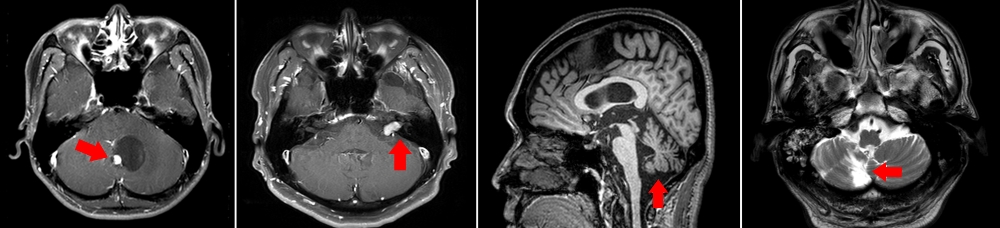

병원에서 이석증이라는 진단을 받아 약물을 꾸준히 복용했지만 전혀 호전이 없었고 최근에는 증상이 더 심해져, 어두운 곳에 가거나 밤거리를 걸을 때면 휘청거리고 균형을 잡을 수 없어 친구들의 부축을 받아야 했다. 주변 권유로 모 대학병원을 찾은 A씨는 MRI 검사 결과 소뇌종양을 진단받고 큰 충격을 받았다.

뇌종양이 있는 경우에도 종양이 서서히 자라면서 어지럼증과 두통을 느끼게 된다. 주로 50대에서 60대에서 많이 발병하긴 하지만 최근에는 젊은 층의 유병율도 높아지는 추세라 안심할 수 없다.

뇌졸중의 경우 고혈압이나 당뇨가 있는 사람에게서 주로 발생하는데 반해 뇌종양은 뚜렷한 원인 및 예방책이 없어 더 무서운 질환이다. 어지럼증과 함께 종양 위치에 따라 말이 어눌해지는 등 언어장애가 나타나거나 엉뚱한 행동을 하기도 한다. 조기진단을 통해 질환의 진행 속도를 늦추고 생존율을 높일 수 있으므로, 증상이 나타날 시 방치하지 말고 병원을 찾아야 한다.